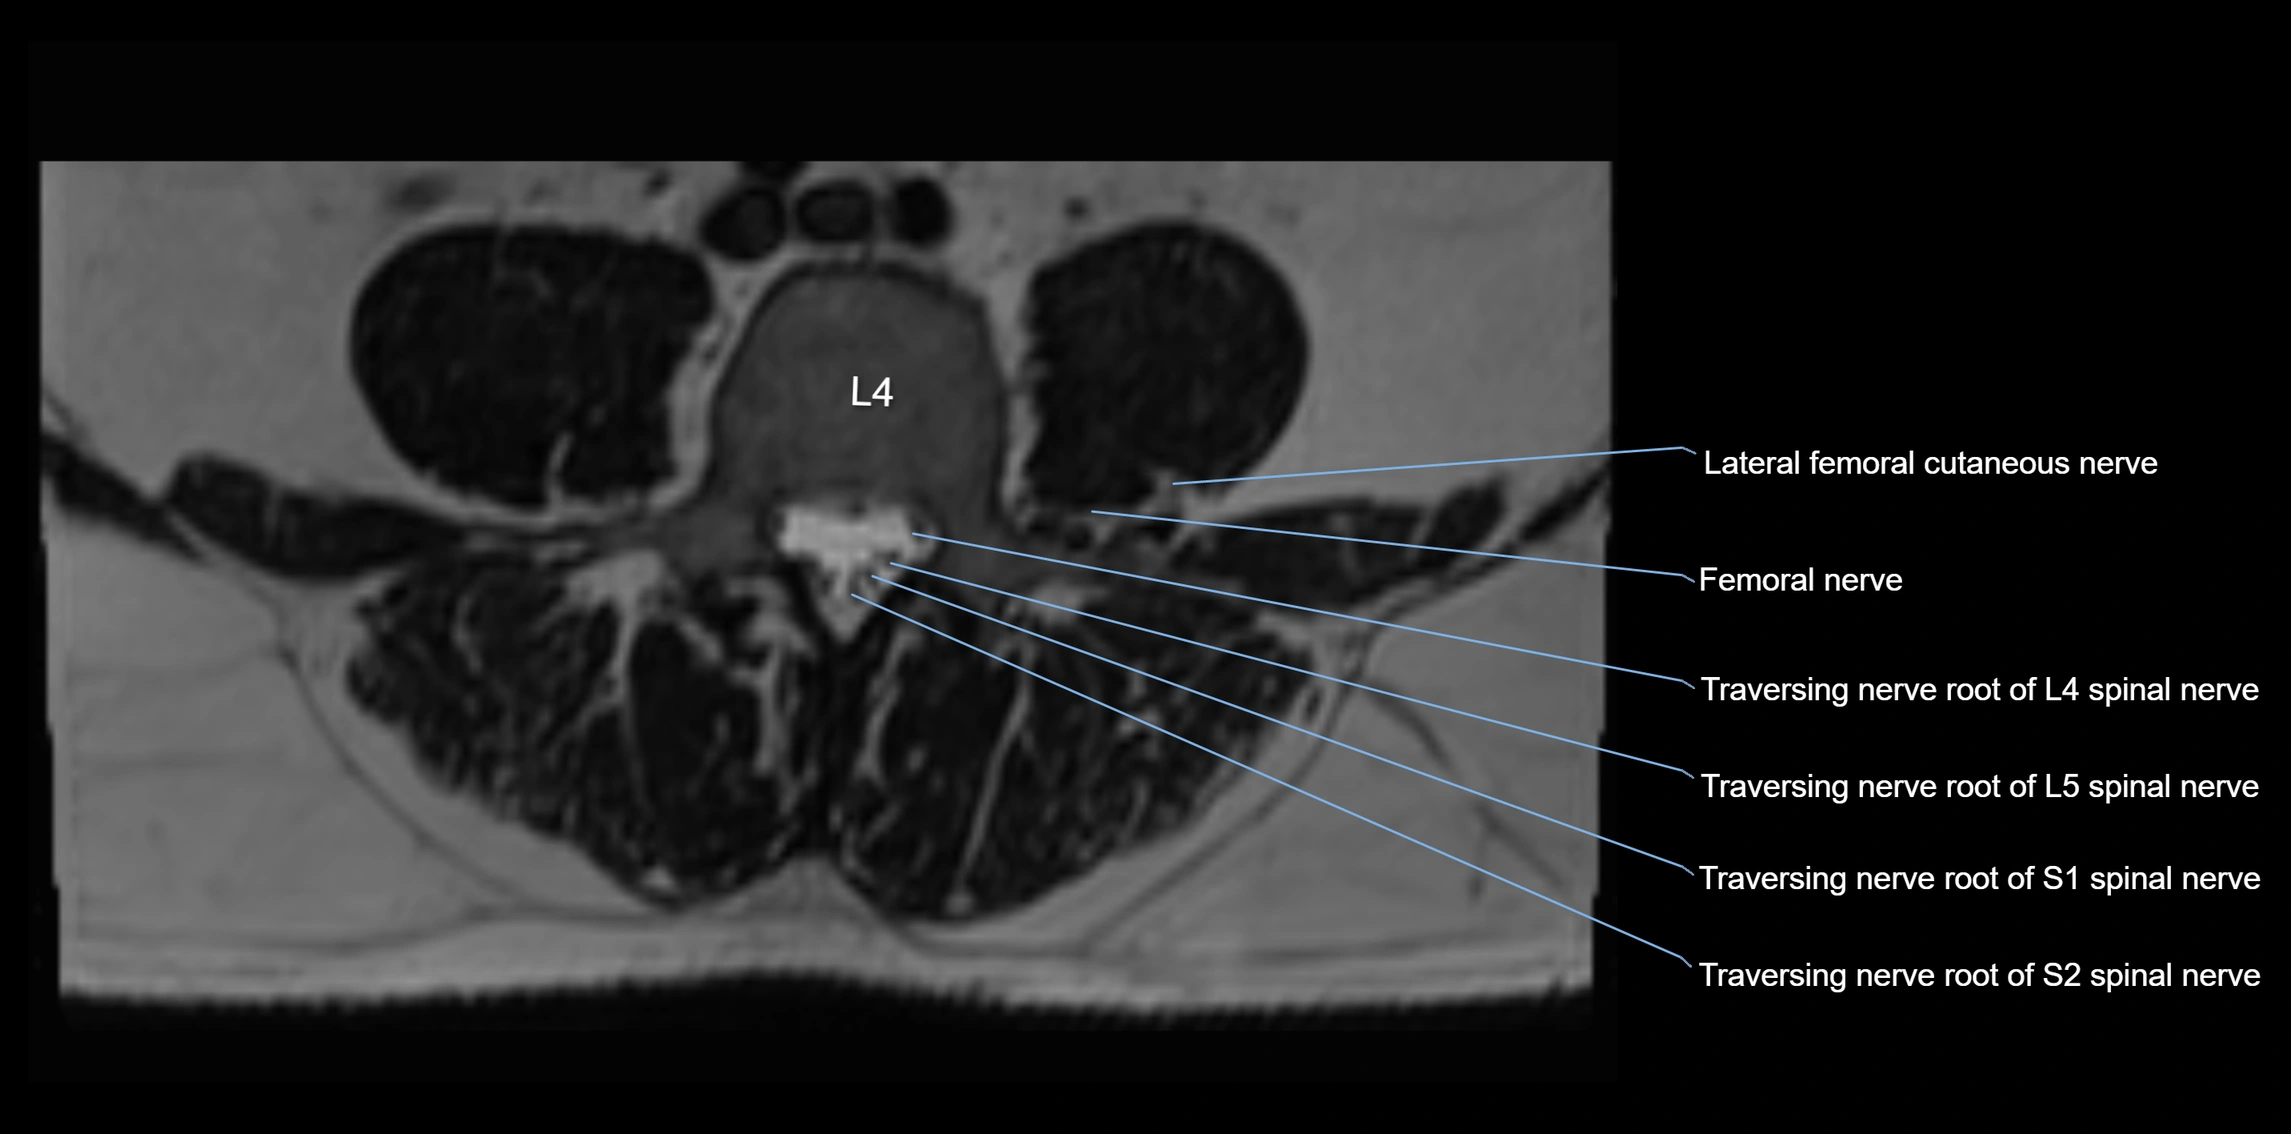

MRI image

image